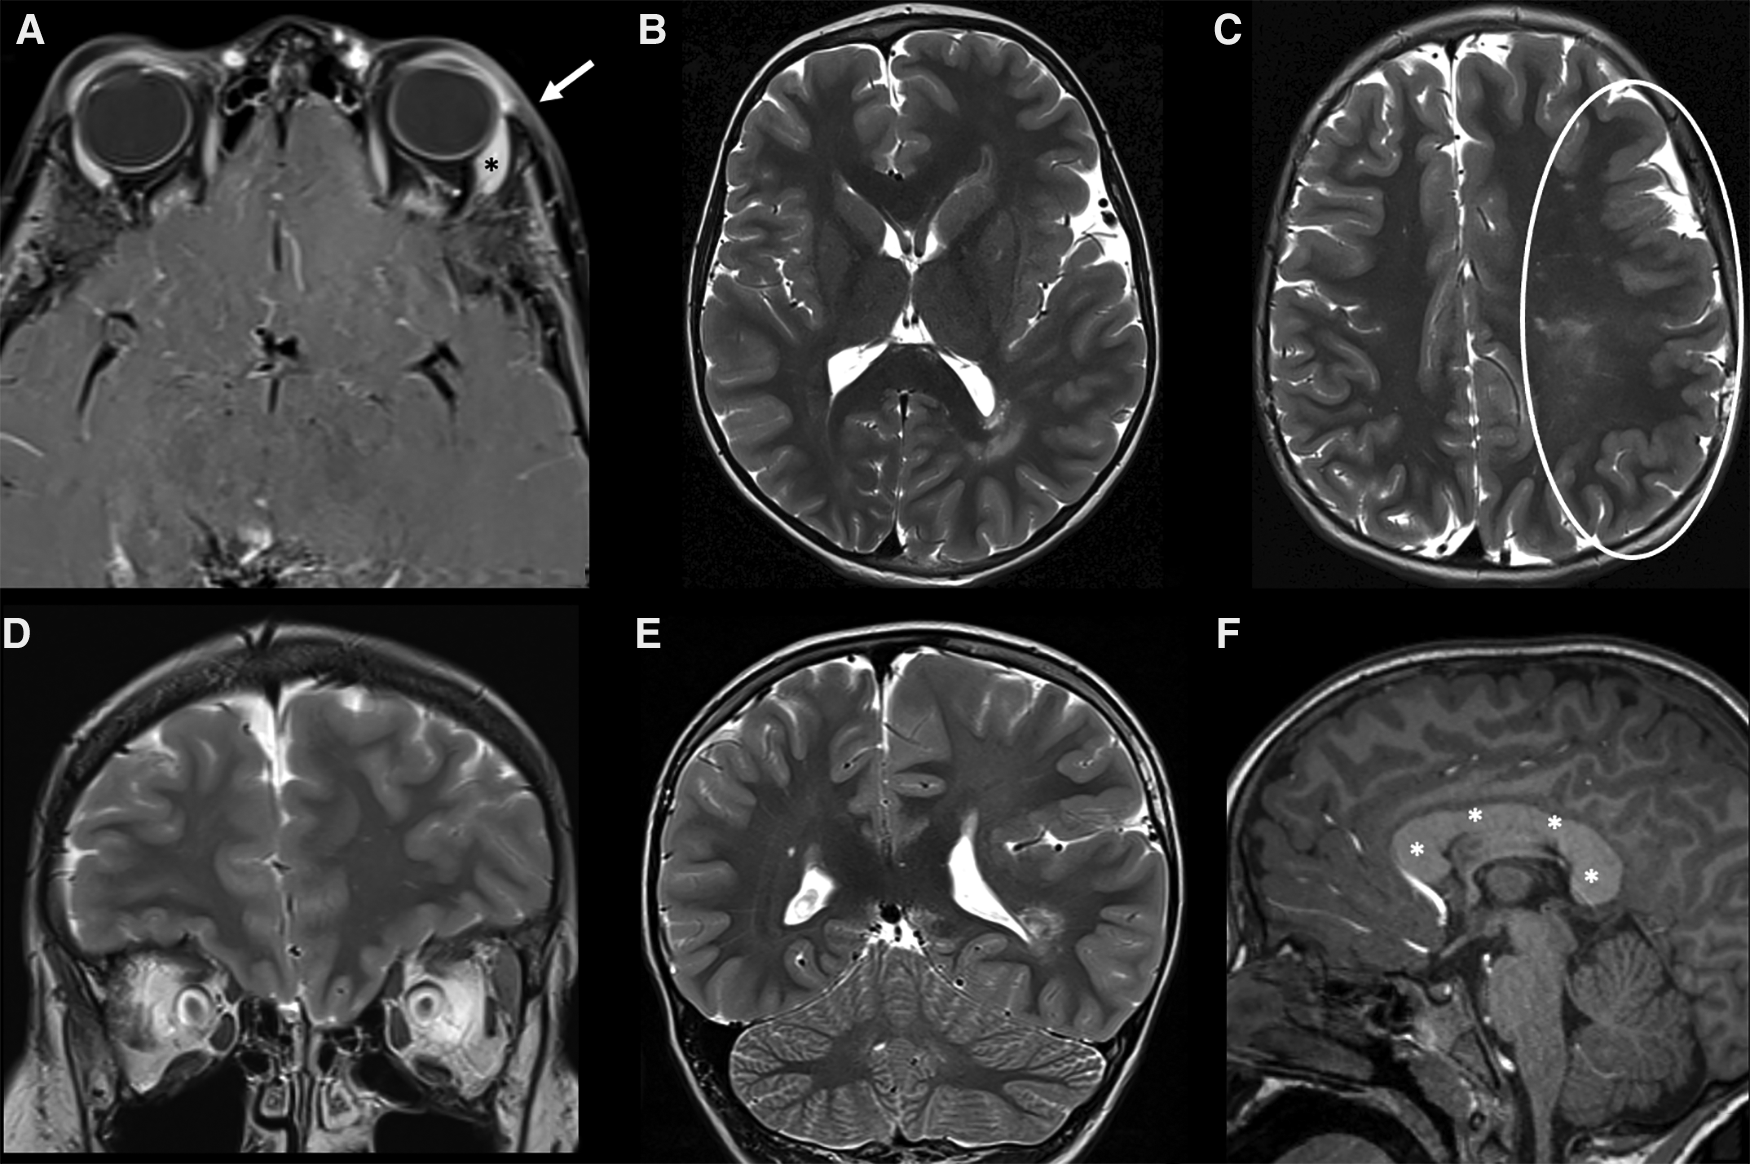

It includes: Posterior fossa abnormalities (Dandy-Walker or cerebellar hypoplasia usually on the same side of the hemangioma) (Figures 5, 6), Hemangioma, Arterial abnormalities (Figure 6), Cardiac anomalies (coarctation of the aorta), Eye defects and Sternal abnormalities (24). Importantly, cerebral arterial abnormalities are the most frequently associated abnormalities in the literature (25) and they are usually located on the same side of the IH and cerebellar findings, supporting the embryological pathogenesis (26). Hence, all patients with suspected PHACE should undergo MRI of the brain and of the cerebral vasculature and should be risk-stratified for acute ischemic stroke (25), although strong evidence for the latter are still lacking.

Figure 6. MRI of 4-month-old girl with a red mass of the left orbit. Axial T2 weighted images (A,B) show a left orbital hyperintense mass (big white arrow in A) with tiny flow-voids involving the extra and intraconal compartments, consistent with infantile hemangioma (IH); on the same sequence the cerebellar atrophy on the ipsilateral side of the IH is also noted (B). Additionally, MR TOF-3D disclosed abnormalities of the intracranial circulation (C). The diagnosis of PHACES was finally made.

Figure 7. MRI of a 3-year-old child with Sturge-Weber syndrome and a capillary malformation (CM) on the left forehead, upper eyelid and periorbital region (V1 distribution). (A,B) On the left there is an increased thickness of the periorbital soft tissues (particularly of the skin and subcutaneous tissue) corresponding to the clinically visible mark, which shows a subtle hyperintensity on axial T2-weighted sequence and a faint but rather homogeneous enhancement on axial post contrast T1 weighted sequences (white arrows in A and B, respectively). (C–E) Typical associated intracranial features of SWS on the same side (left) of the CM, including atrophy of the cerebral hemisphere with enlargement of subarachnoid spaces (especially in the frontal, insular, parietal and occipital regions, white circle in C), cortical gyral hypointensities due to calcifications on SWI (white arrow in D), contrast enhancement of the leptomeningeal angioma and choroidal plexus hypertrophy on axial post-Gadolinium T1 weighted sequence (black arrow and arrowhead in E, respectively). A subtle enhancement of the left frontal bone is also evident (white arrowhead in E), due to the intra-osseus extension of the overlying CM.

Figure 8. MRI of a 7-year-old Male child with left-sided facial hypertrophy with multiple reddish macules on the face and left orbit, with a clinical suspicion of macrocephaly-capillary malformation (M-CM). (A) A slight thickening associated with subtle enhancement of the skin and subcutaneous tissue (white arrow) of the left orbit is noted on fat-sat post-contrast T1 images, corresponding to one of the clinically visible macules. A slight hypertrophy of the left lacrimal gland is also noted (asterisk). (B–E) Axial (B,C) and coronal (D,E) images of the brain revealed a marked asymmetry of the cerebral hemispheres, with left being larger than right consistent with left hemimegalencephaly. The cortex of the enlarged hemisphere is also diffusely polymicrogyric (white circle in C). (F) on the post contrast sagittal T1 an abnormal thickness of the entire corpus callosum is also evident (white asterisks). A mosaic mutation of PIK3CA gene was discovered, confirming the clinical suspicion of M-CM.